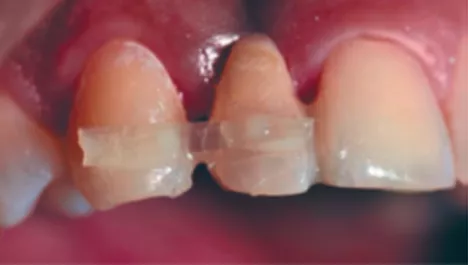

PTQSF_12

FIG 12:

Tooth #12 and #11 now joined together which give a natural appearance but further strengthening is needed from a bio mechanical perspective for longevity of the restoration